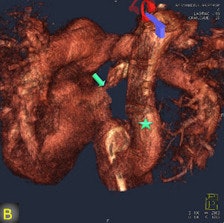

FD-CT, combined with image fusion to overlay 3D reconstructions on fluoroscopic images during catheter-based interventions, was useful -- and occasionally irreplaceable -- for deciphering the complex anatomy of congenital heart disease, wrote authors Dr. Martin Glöckler, Dr. Andreas Koch, and colleagues from University Hospital Erlangen in Erlangen, Germany.

"In particular, the possibility of acquiring 3D vascular volumes with high resolution and the option to visualize complex spatial relationships from any desired angle promises clinical utility to plan and guide interventional and surgical procedures," they wrote. (Eur. Radiol, 28 July 2011).

"The fusion of 3D reconstructions with live fluoroscopic images during catheterization may help to find the ideal fluoroscopic angulation during catheter-based interventions, to achieve difficult vascular crossings by the wire or the catheter, to choose the most appropriate material for catheterization, and to define and control optimized positioning of implants such as stents or valve prostheses," Glöckler and colleagues explained.

"One unique feature of FD-CT is the possibility of merging 3D reconstructions with the real-time fluoroscopic image," a potentially useful way to identify ideal C-arm angulations for achieving wire passage for atypical vascular crossings, and to optimally depict the implant position of coils, plugs, stents, and valves," Glöckler and colleagues wrote. "In fact, image fusion of 3D reconstructed FD-CT images with the live fluoroscopic image was frequently rated as 'very useful' (57.4%)."